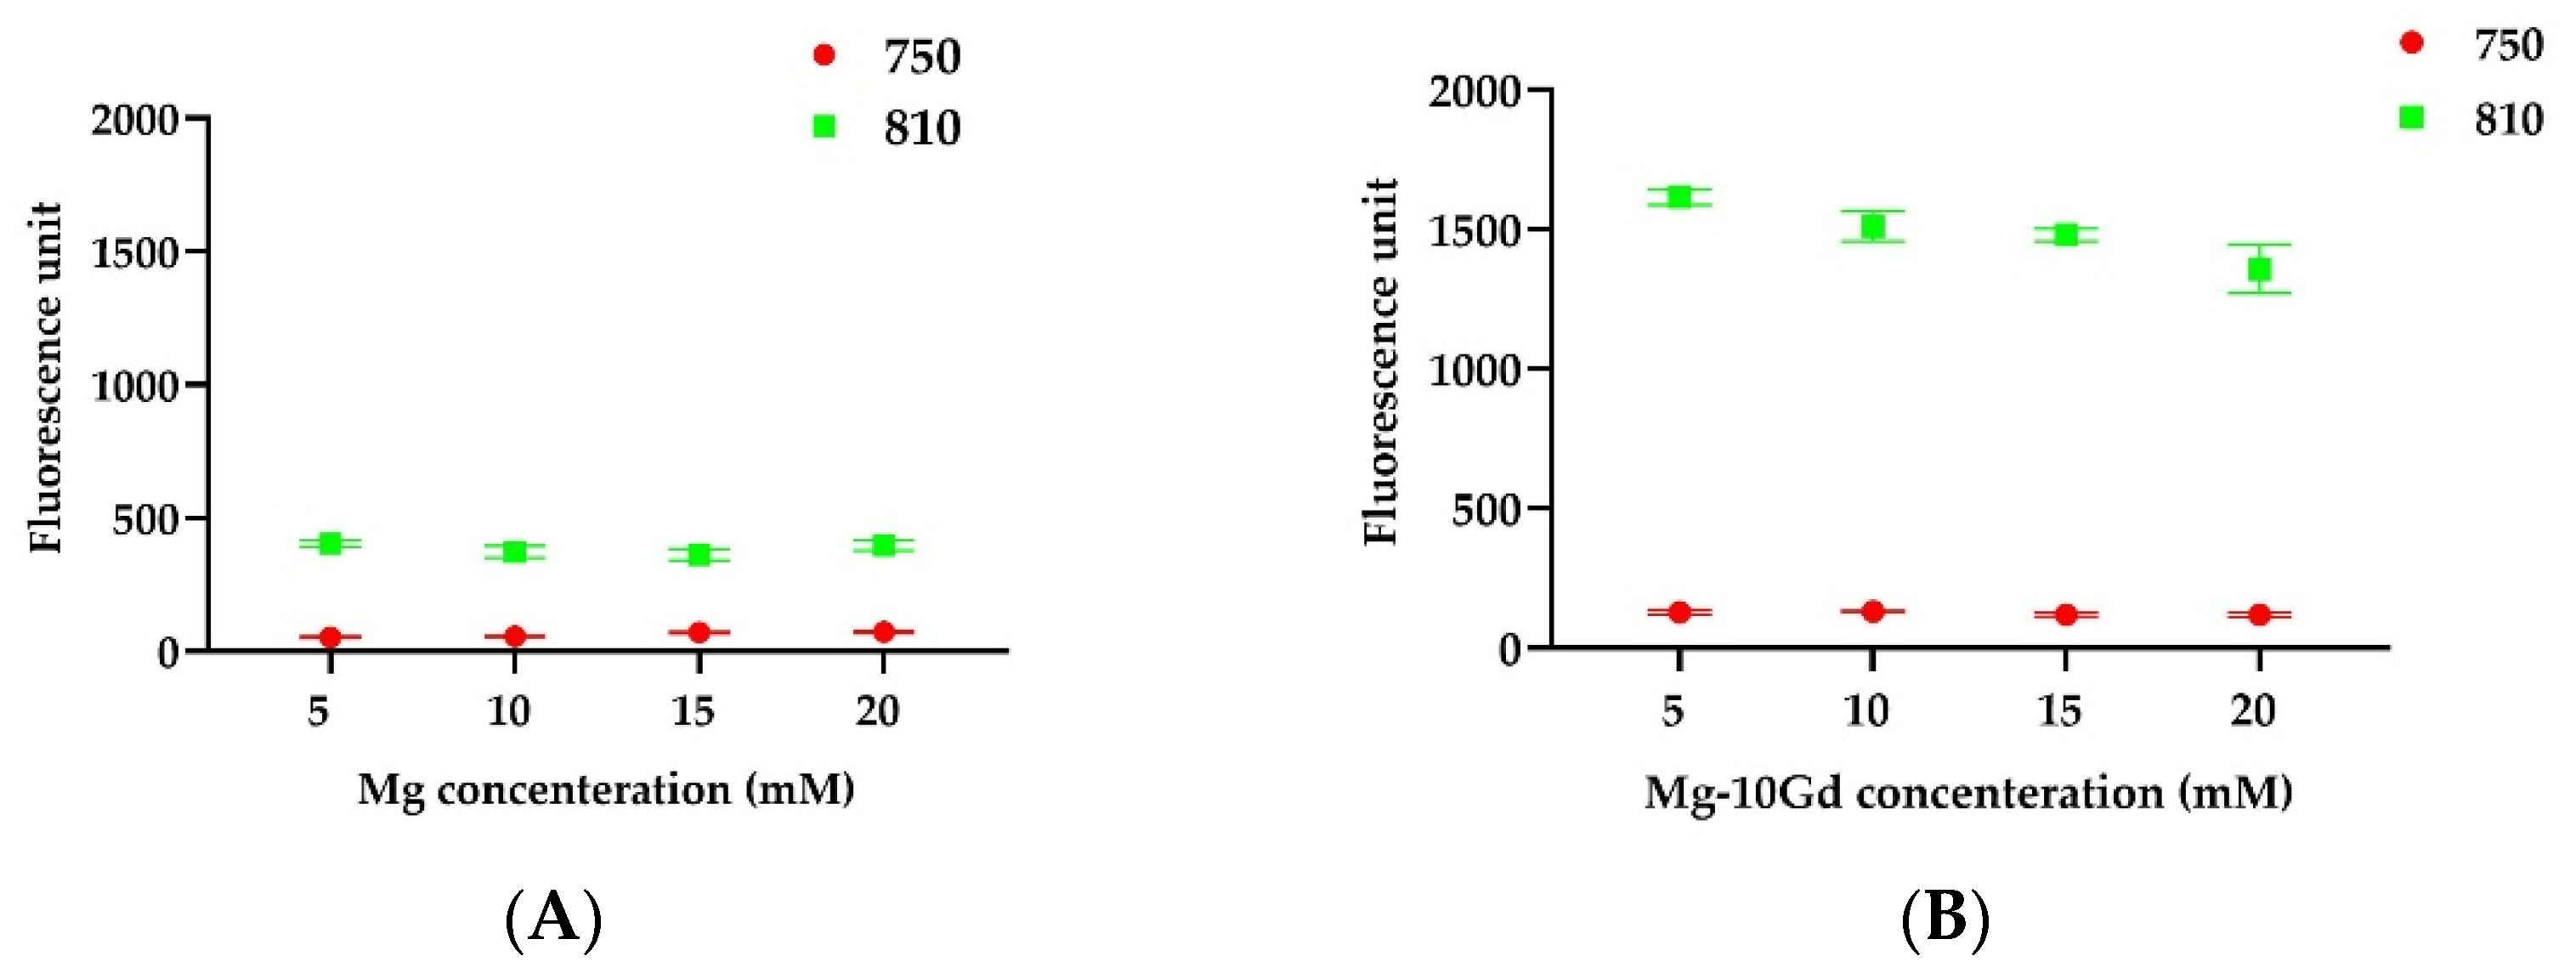

2.1.1. Fluorometric Analysis

4.3.1. Fluorescence Measurement to Analyze the Ion Effect on Liposomal ICG Fluorescence